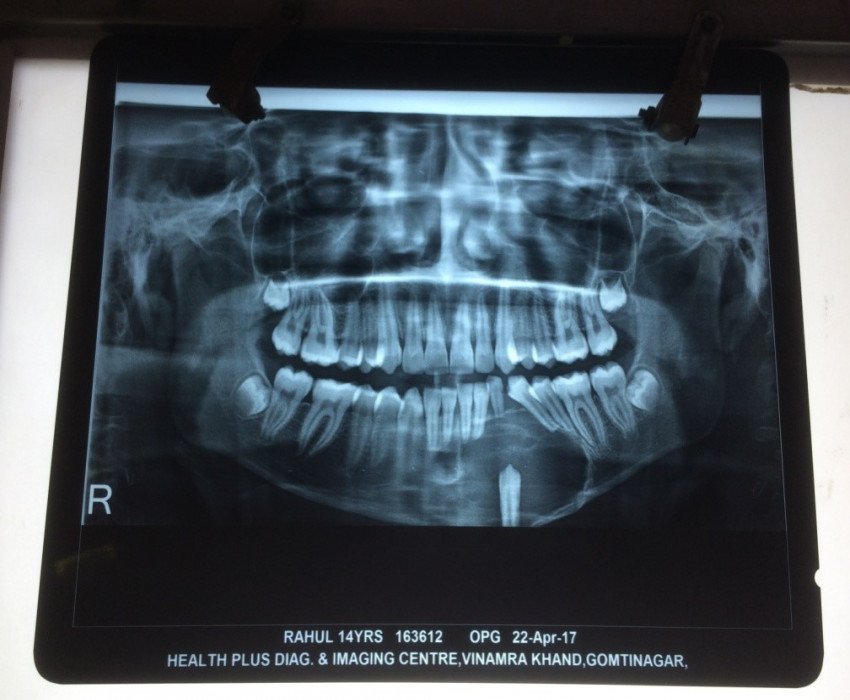

SURGICAL MANAGEMENT OF Maxillofacial Pathology: